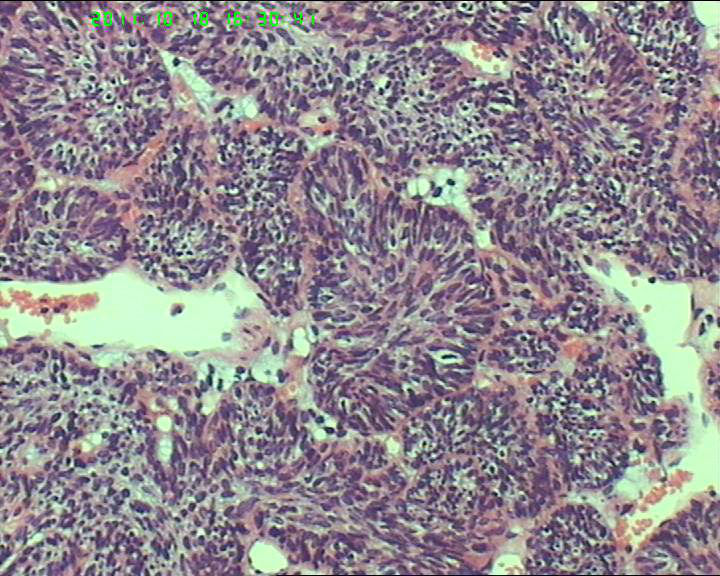

70岁女性体检发现膀胱肿物,是癌吗?

膀胱后壁一2*1cm大小肿物